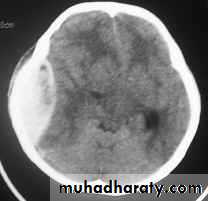

c. Intracerebral Haematoma

This is the least common of traumatic haematoma.They are due to areas of traumatic contusion coalescing into a contusional haematoma.

Disrupted cerebral tissue release thromboplastins that potentiate haemorrhage.

CT scan: appear as hyperdence lesions with associated mass effect and midline shift.Large intracerebral haematomas should be evacuated unless the patient’s neurological state is improving.

Small inracerebral haematomas may not require removal, but be aware that they can expand.